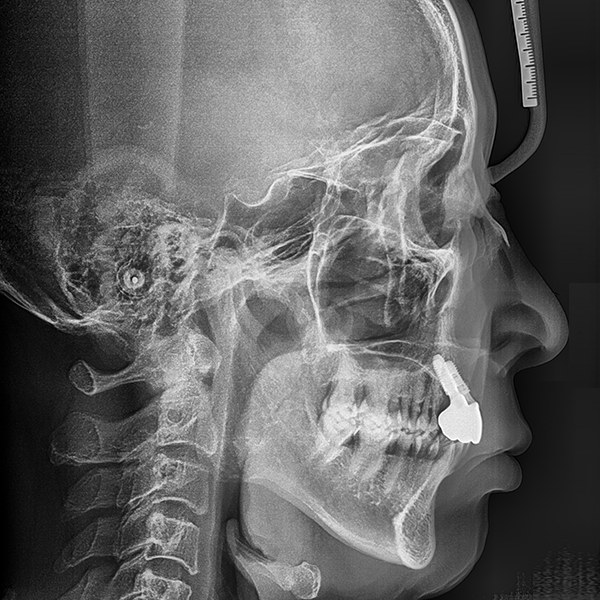

上顎/前牙部位 / 3顆以下 / 補骨|高血壓

案例.110 60多歲 李*桂 2020-01-20 / 2020-3-21